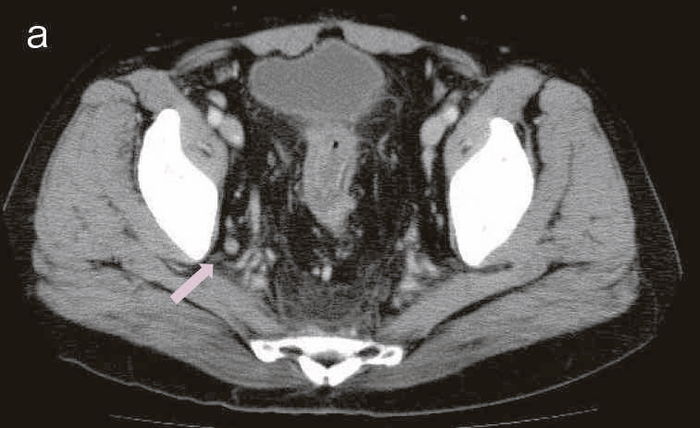

図37 肛門部所見と生検組織採取部位(Jack-knife position)

図上が背側(6時方向),下が腹側(0時方向)。肛門の右後方(7時方向)にある2次口からの分泌物の細胞診はclass Ⅲbであった。全身麻酔下の生検ではその2次口の原発口からadenocarcinomaが検出された。

図38 骨盤部MRI

術前の骨盤部MRIでは右側の痔瘻瘻管と,左側の瘻管,周囲のリンパ節腫大を認めた。

明らかな癌を示す所見は不明であった。